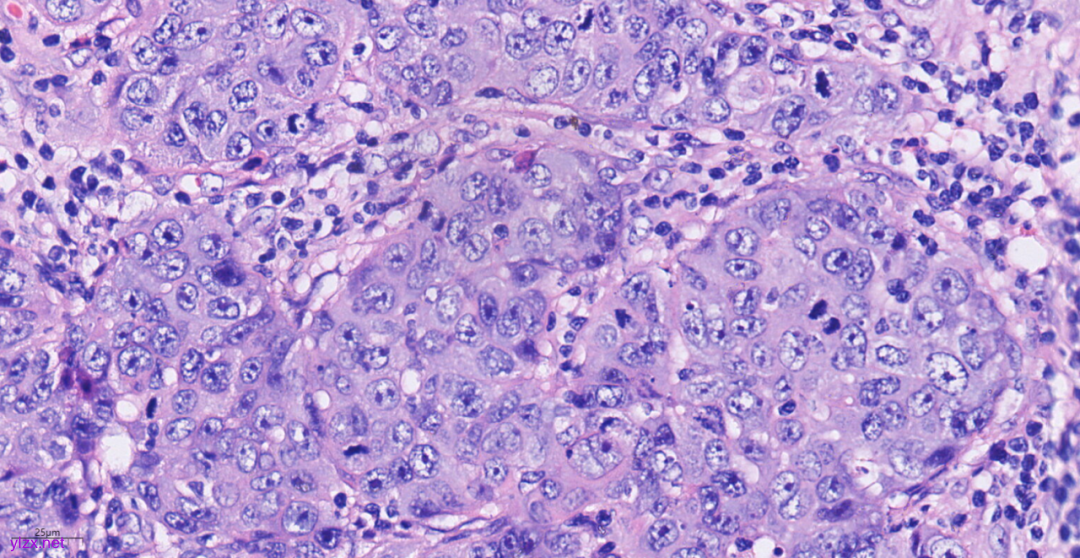

3.2镜下观(图3-图9):

低倍镜下可见卵巢肿物呈囊,中倍镜下,囊壁见分化成熟的多胚层成分,成熟型囊性畸胎瘤区域可见皮肤(正常鳞状上皮及其表明角化物)及其附属器成分(皮脂腺、汗腺及毛囊),局部囊壁表面可见由正常鳞状上皮-原位癌-鳞状细胞癌逐渐过渡;在鳞状细胞癌区域,囊壁增生的纤维结缔组织中可见肿瘤细胞呈巢状向下浸润性生长,也向囊腔内乳头状生长,局部癌巢中央可见角化珠及坏死;高倍镜下,鳞癌成分肿瘤细胞大小不等,细胞排列紊乱,细胞中-重度异型,核大深染,略呈空泡状,核仁明显,核分裂象易见,伴角化珠形成。

图3 低倍镜下可见卵巢肿物呈囊。

图4 中倍镜下,成熟型囊性畸胎瘤区域可见正常鳞状上皮、皮脂腺、汗腺及毛囊。

镜下观:

MCT-SCC在形态学上分为MCT和鳞状细胞癌两种成分,其中MCT镜下可见由发育成分化良好的外胚层、内胚层和中胚层组织,如牙齿、头发、骨骼和皮脂腺。SCC镜下见增厚的囊壁处有鳞状细胞癌成分,表现为异型增生的鳞状上皮细胞突破基膜向间质延伸,增生的纤维结缔组织中见肿瘤细胞排列成巢状,细胞大小不等,排列紊乱,核分裂象易见;可见同心圆排列的角化珠。病理医师应对标本充分取材进一步提高其诊断水平。